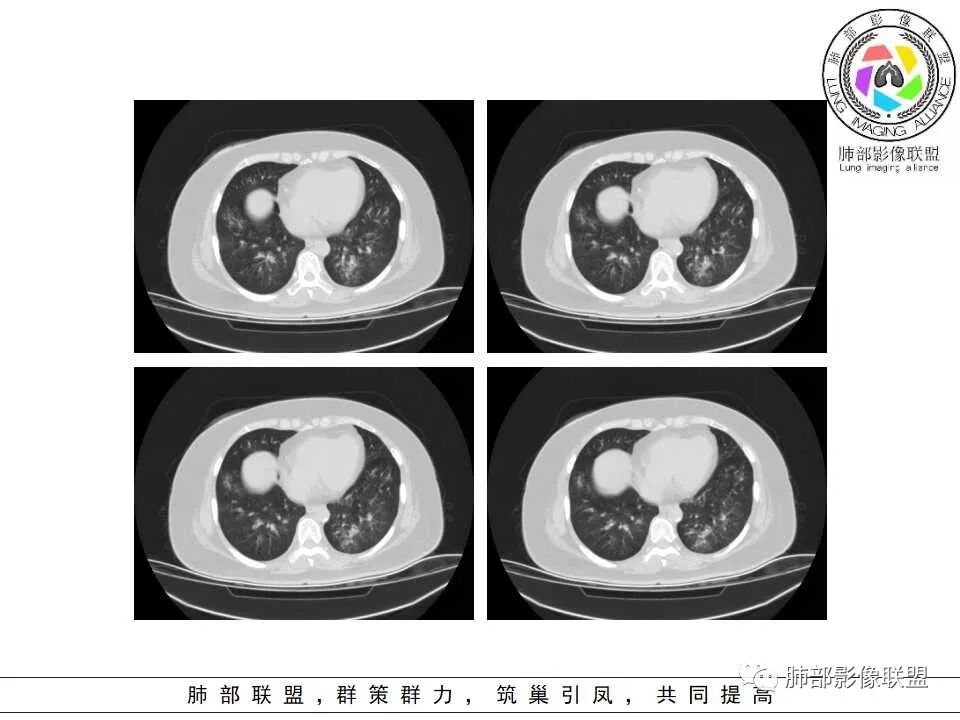

1.病灶沿支气管分布的特点相当明显,相应支气管壁广泛增厚。这种与支气管关系极为密切的片影和/或结节影,常高度提示气道相关感染,如支气管肺炎。

2.患者两肺多发病变,具有广泛性。如此广泛分布更多见于免疫低下的机会性感染。

3.支气管壁广泛增厚对气道侵袭性曲霉病具有一定的提示意义。注意患者没有支气管扩张,临床也未提供IGE等实验室资料。

4.老年女性患者,咳嗽少痰,伴喘息气短8天。注意患者没有发热,中毒症状不明显。既往糖尿病、高血压病史。

炎性指标升高,头孢等药物覆盖疗效不佳。

白细胞升高异乎寻常,注意病史已有两年之久,这至少提供两方面信息:

1)与本次肺部感染不能直接密切对应或相关联,能想象吗,这样的感染持续两年?

2)患者存在血液系统疾病的可能性,如白血病,这应当进一步查实。

一,气道侵袭性曲霉病(PNTA)

1.器官支气管管套样壁增厚和/或支气管扩张,注意壁增厚较均匀,和/或伴有播散性小片影及结节影,注意这些小片影或结节影边界有时较普通炎性病灶清楚。

2.可以阻塞支气管造成肺不张而酷似中央型肺癌。偶而可呈大范围毛玻璃样影。

3.易形成空洞,常无液平面。注意哪些一两周内出现的多发空洞病灶,形成空洞也往往靠边。